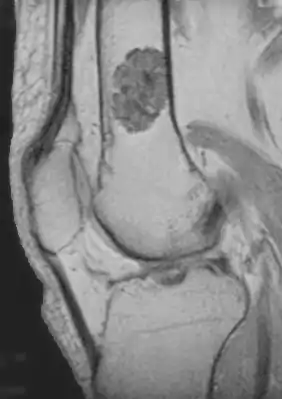

| Chondroblastoma[2] | ![]() | |